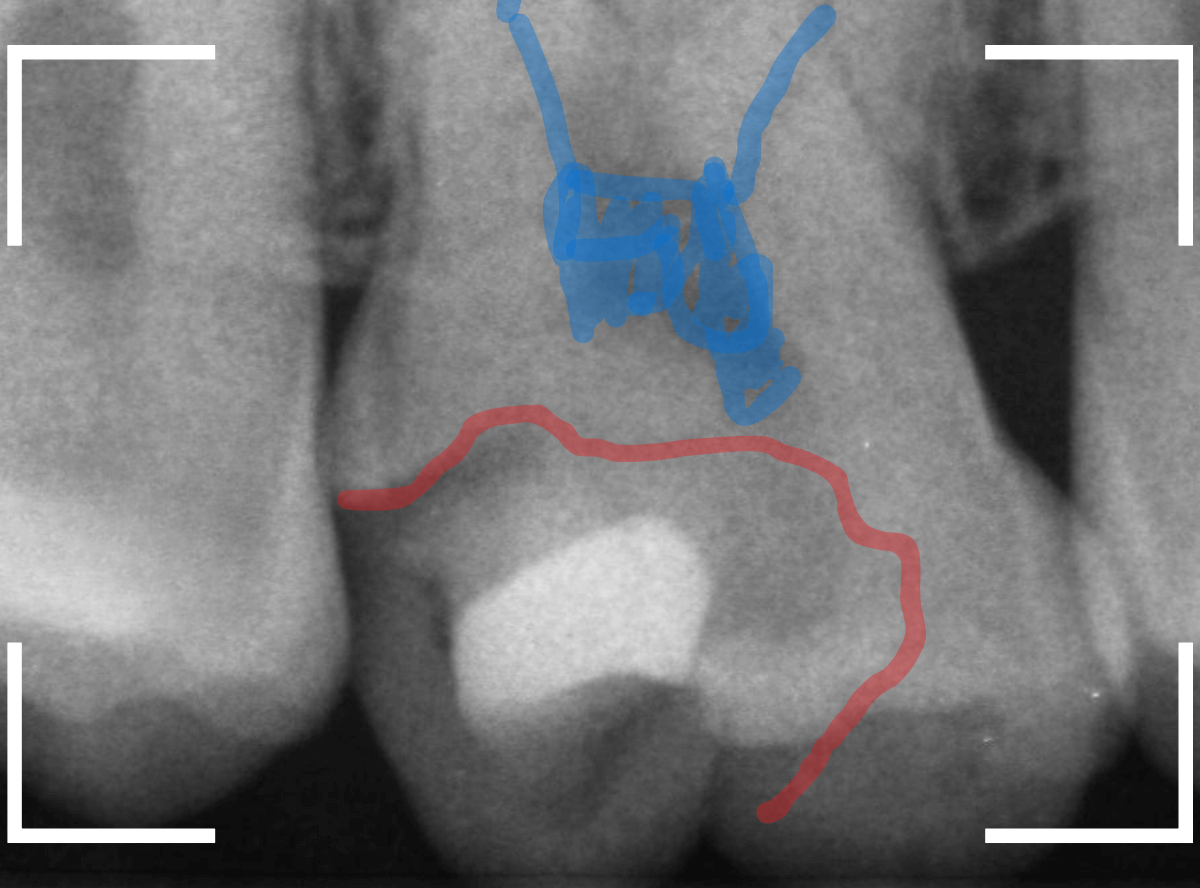

レントゲン写真で確認します。

青い線が歯の神経です。

赤い線が虫歯と思われる部分です。

思った通り、神経に達してしまいそうな大きな虫歯です。

患者さんには、神経を取る治療が必要な可能性が高い事を説明します。